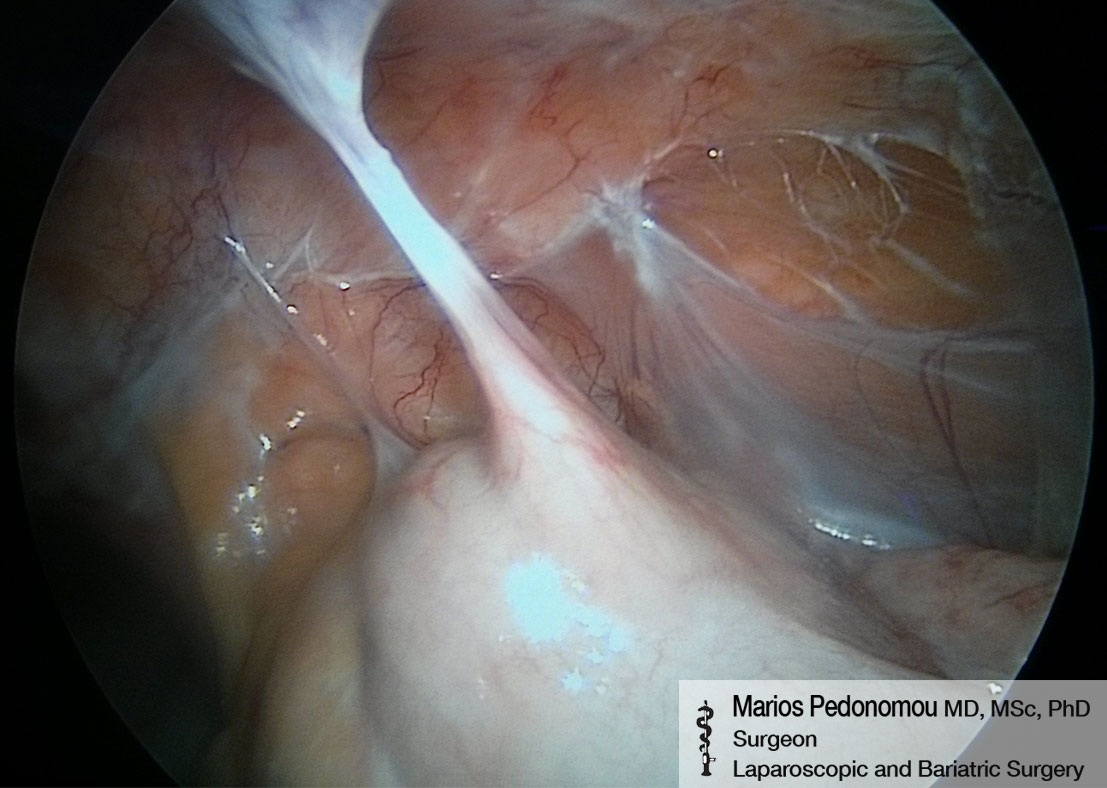

Εσωτερική Κήλη

Πολλές φορές λόγω προηγούμενων επεμβάσεων ή τραυμάτων μπορεί να σχηματιστούν κοιλότητες ή στόμια μέσα στην κοιλιακή χώρα. Μέσα στους χώρους αυτούς μπορεί να εισέλθουν έλικες του λεπτού εντέρου και δυνητικά να εγκλωβιστούν, να περισφιχθούν και να νεκρωθούν. Ο ασθενής θα βιώσει συμπτώματα εντερικής απόφραξης, όπως έντονο κοιλιακό άλγος, αναγούλες και εμέτους και διάταση κοιλίας. Η εσωτερική κήλη χαρακτηρίζεται ως χειρουργικό επείγον και απαιτεί άμεση χειρουργική αντιμετώπιση.